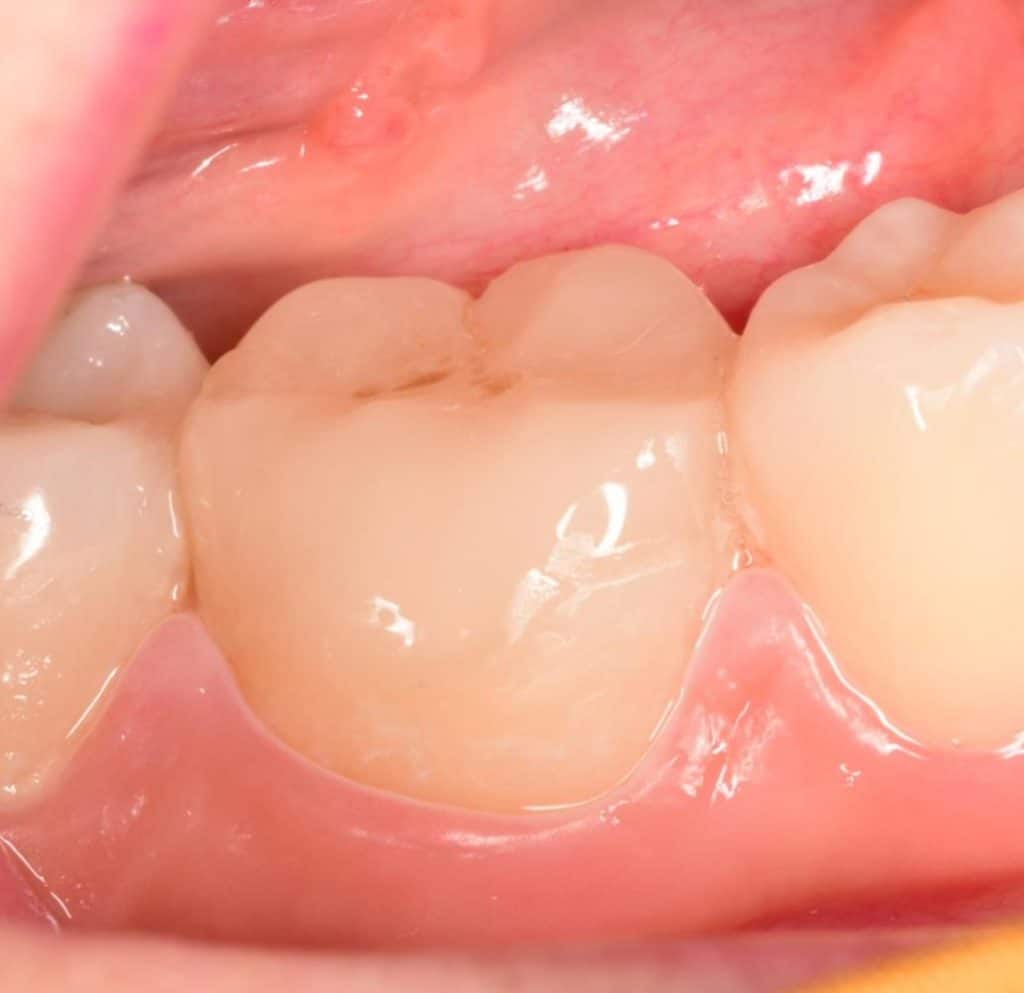

7 months follow-up

2 years follow-up